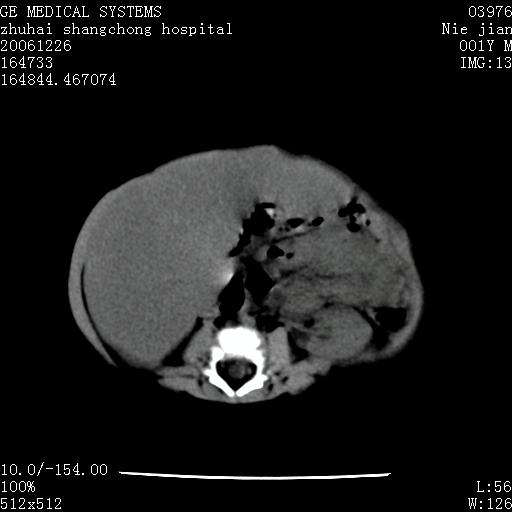

3个月婴儿腹胀来看。

肝各叶比率失调,明显增大,实质内大量脂肪侵润。另:左侧肾上腺区较大类圆形低密度肿块,左肾明显受压 下移。多考虑:1 左侧肾上腺神经母细胞瘤!2 肝弥漫性损伤!

肝各叶比率失调,明显增大,实质内见多发团块状低密度灶。另:左侧肾上腺区较大类圆形肿块,左肾明显受压 下移。多考虑:1 左侧肾上腺神经母细胞瘤!2 肝脏多发转移!

鉴别诊断:肾母细胞瘤,好发1-3岁,肾母细胞瘤是发生在肾脏,又称肾胚瘤,肾脏本身增大。而神经母细胞瘤也称成神经细胞瘤,好发1-2岁,多发生在肾上腺髓质。肾脏本身表现受压向下移位。

【影像特征】

1、肝明显增大,肝弥漫性低密度灶。

2、肾上腺区见类圆形肿块,其内密度不均,见片状偏高密度。

【诊断】

1、肝弥漫性病变,考虑急性肝炎致广泛脂肪浸润可能性大。

2、肾上腺区占位,假性肿瘤?肾上腺血肿(感染所致)?

1、关键着眼点:肝脏弥漫性病变内有没有走形的血管,仔细看部分低密度内有血管影(要有增强扫描作为证据就好了),说明并非肿瘤样病变,而是脂肪浸润。即可能不是转移瘤或原发肿瘤,低密度的形态上看,是片状,也不像肿瘤。

2、儿童肝炎最常见的是感染,有时食入性损害或药物也可致肝脏炎症,肝炎致大空泡型脂肪变性,是一种无痛性疾病,无症状,病因有营养异常、代谢性疾病、药物及病毒感染。所以脂肪变性与感染有关。

3、肝炎的结局是肝硬化,而恰恰一年后复查,已有肝硬化表现。肿瘤一般那会消失,那叫奇迹。

4、肾上腺出血也可见于败血症及感染,通常包块在数周内消失,ct表现包块内有偏高密度,可能是亚急性血肿的表现。假性肿瘤即腹部肠管积液、扩张血管及邻近结构的伪像。自然会消失。

5、因此,感染可以贯穿一切,解释一切。肿瘤自然消退?可能吗?那些应要无道理的创造奇迹的事情会那么容易发生吗?